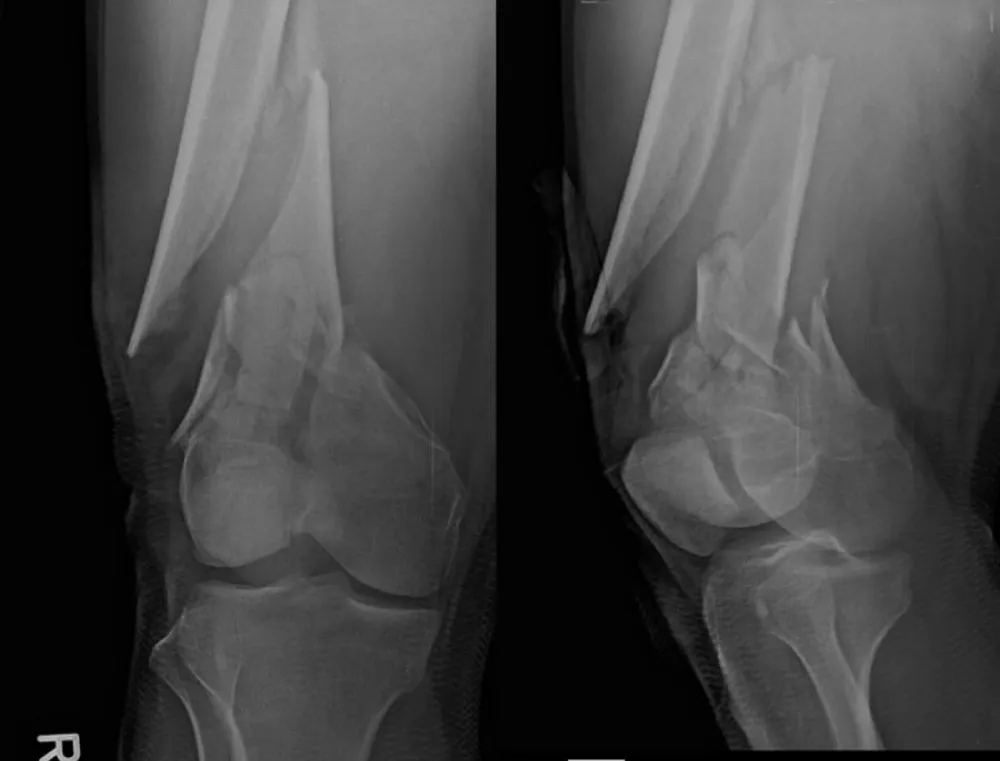

Figure 1: A–D: Hyperacute unilateral decompensation, 12‑minute rescue, and orthopedic context. A: pre‑intervention chest radiograph with right‑lung opacification/volume loss. B: post‑decompression ~T+12 min (endotracheal tube in situ) with re‑expansion and improved aeration. C: oxygenation trajectory (0–30 min) showing PaO₂/FiO₂ 92→308 within 12 minutes; induction at T+30 min and ORIF at T+90 min. D: representative pre‑operative distal femur views demonstrating bilateral, comminuted metaphyseal–diaphyseal extension. Bedside LUS guided targeted decompression with initial water‑seal to limit early suction and REPE risk [19-22]; small‑bore use aligns with trauma literature [14-16,24]; timing followed EAC once physiology normalized [17,18,23]; the distal femur patterns provide a plausible V/Q amplifier consistent with FES imaging reviews [13].

Figure 2: Pre-operative imaging of distal femur fractures. Representative lateral views demonstrate bilateral open distal femur fractures (right Gustilo‑Anderson II; left I).

Figure 3: Additional pre-operative oblique/lateral projections detailing comminution and distal extension.